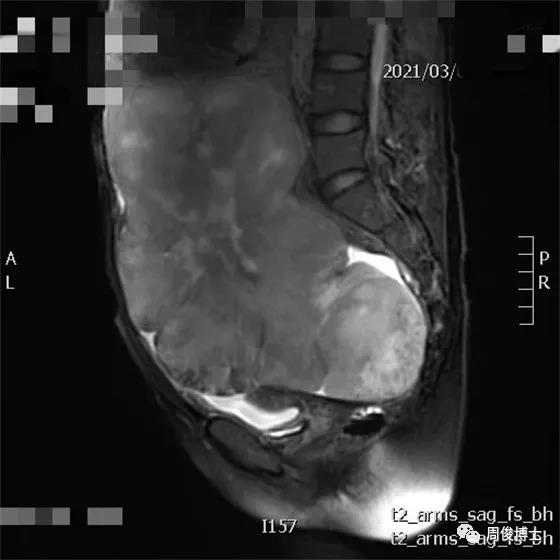

2021年3月,治療前基線,腫瘤巨大,腸道擠成一條線,子宮被壓成小蘿卜干,還有腹水